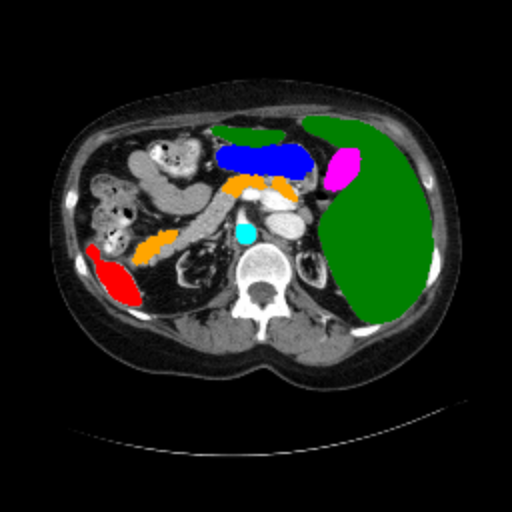

Figure 3 presents a qualitative comparison of segmentation performance on examples from the Synapse, BTCV, ACDC, and ISIC17 datasets. The first two examples (from Synapse) highlight variations in segmentation performance among U-Net, TransUnet, Mamba-Unet, and Swin-Unet. While Swin-Unet performs well in the first example, its performance decreases in the second example, particularly in segmenting the organ highlighted in blue. Additionally, it misclassifies background regions as the class highlighted in orange. In contrast, our approach demonstrates high robustness in segmenting all classes accurately and aligning well with the ground truth masks.

Refer to caption Refer to caption Refer to caption Refer to caption Refer to caption Refer to caption Refer to caption

Slice GT Unet TransUnet Mamba-Unet Swin-UMamba MambaCAFU-V1

Figure 3: Visual comparison of segmentation examples from Synapse (first two examples), BTCV (3-4 examples), ACDC (5th example) and ISIC17 (last example). Columns: input slice, ground truth, Unet, TransUnet, Mamba-Unet, Swin-UMamba, and MambaCAFU-V1.